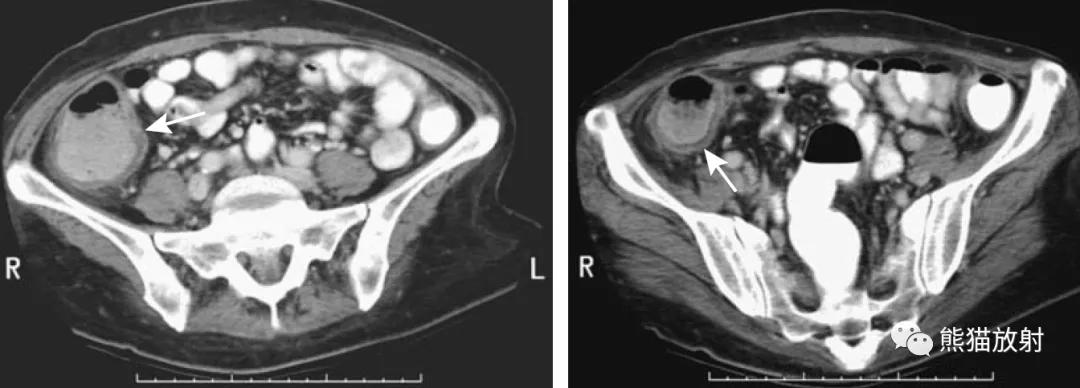

乙状结肠憩室炎。CT(A)和MR(B,C)图像。多发憩室,相应肠壁增厚、周围间隙混浊,不全肠梗阻。

疑急性阑尾炎的患者,右半结肠癌并穿孔(箭头)。周围软组织肿块内坏死并气体影,类似阑尾脓肿表现。